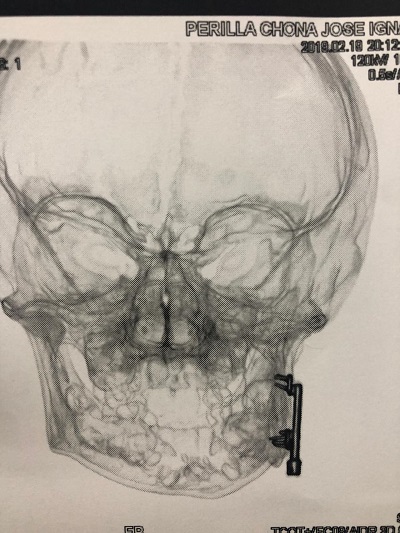

Al ser valorado por los especialistas, le fue diagnosticado una microsomía facial producto de trauma por múltiples cirugías realizadas al menor desde su nacimiento, por lo que se determinó realizar varios estudios de tomografía, donde se evidencia una deformación.

“La cirugía tuvo una duración de dos horas y media, y el menor permaneció 17 días en la unidad de servicios de salud porque cada día debía realizarse una distracción osteogénica, que consiste en activar dispositivos que se encuentran alojados en la mandíbula, dependiendo de la cantidad de hueso que se desea prolongar”, explicó Teomelila Guerra, médico maxilofacial.